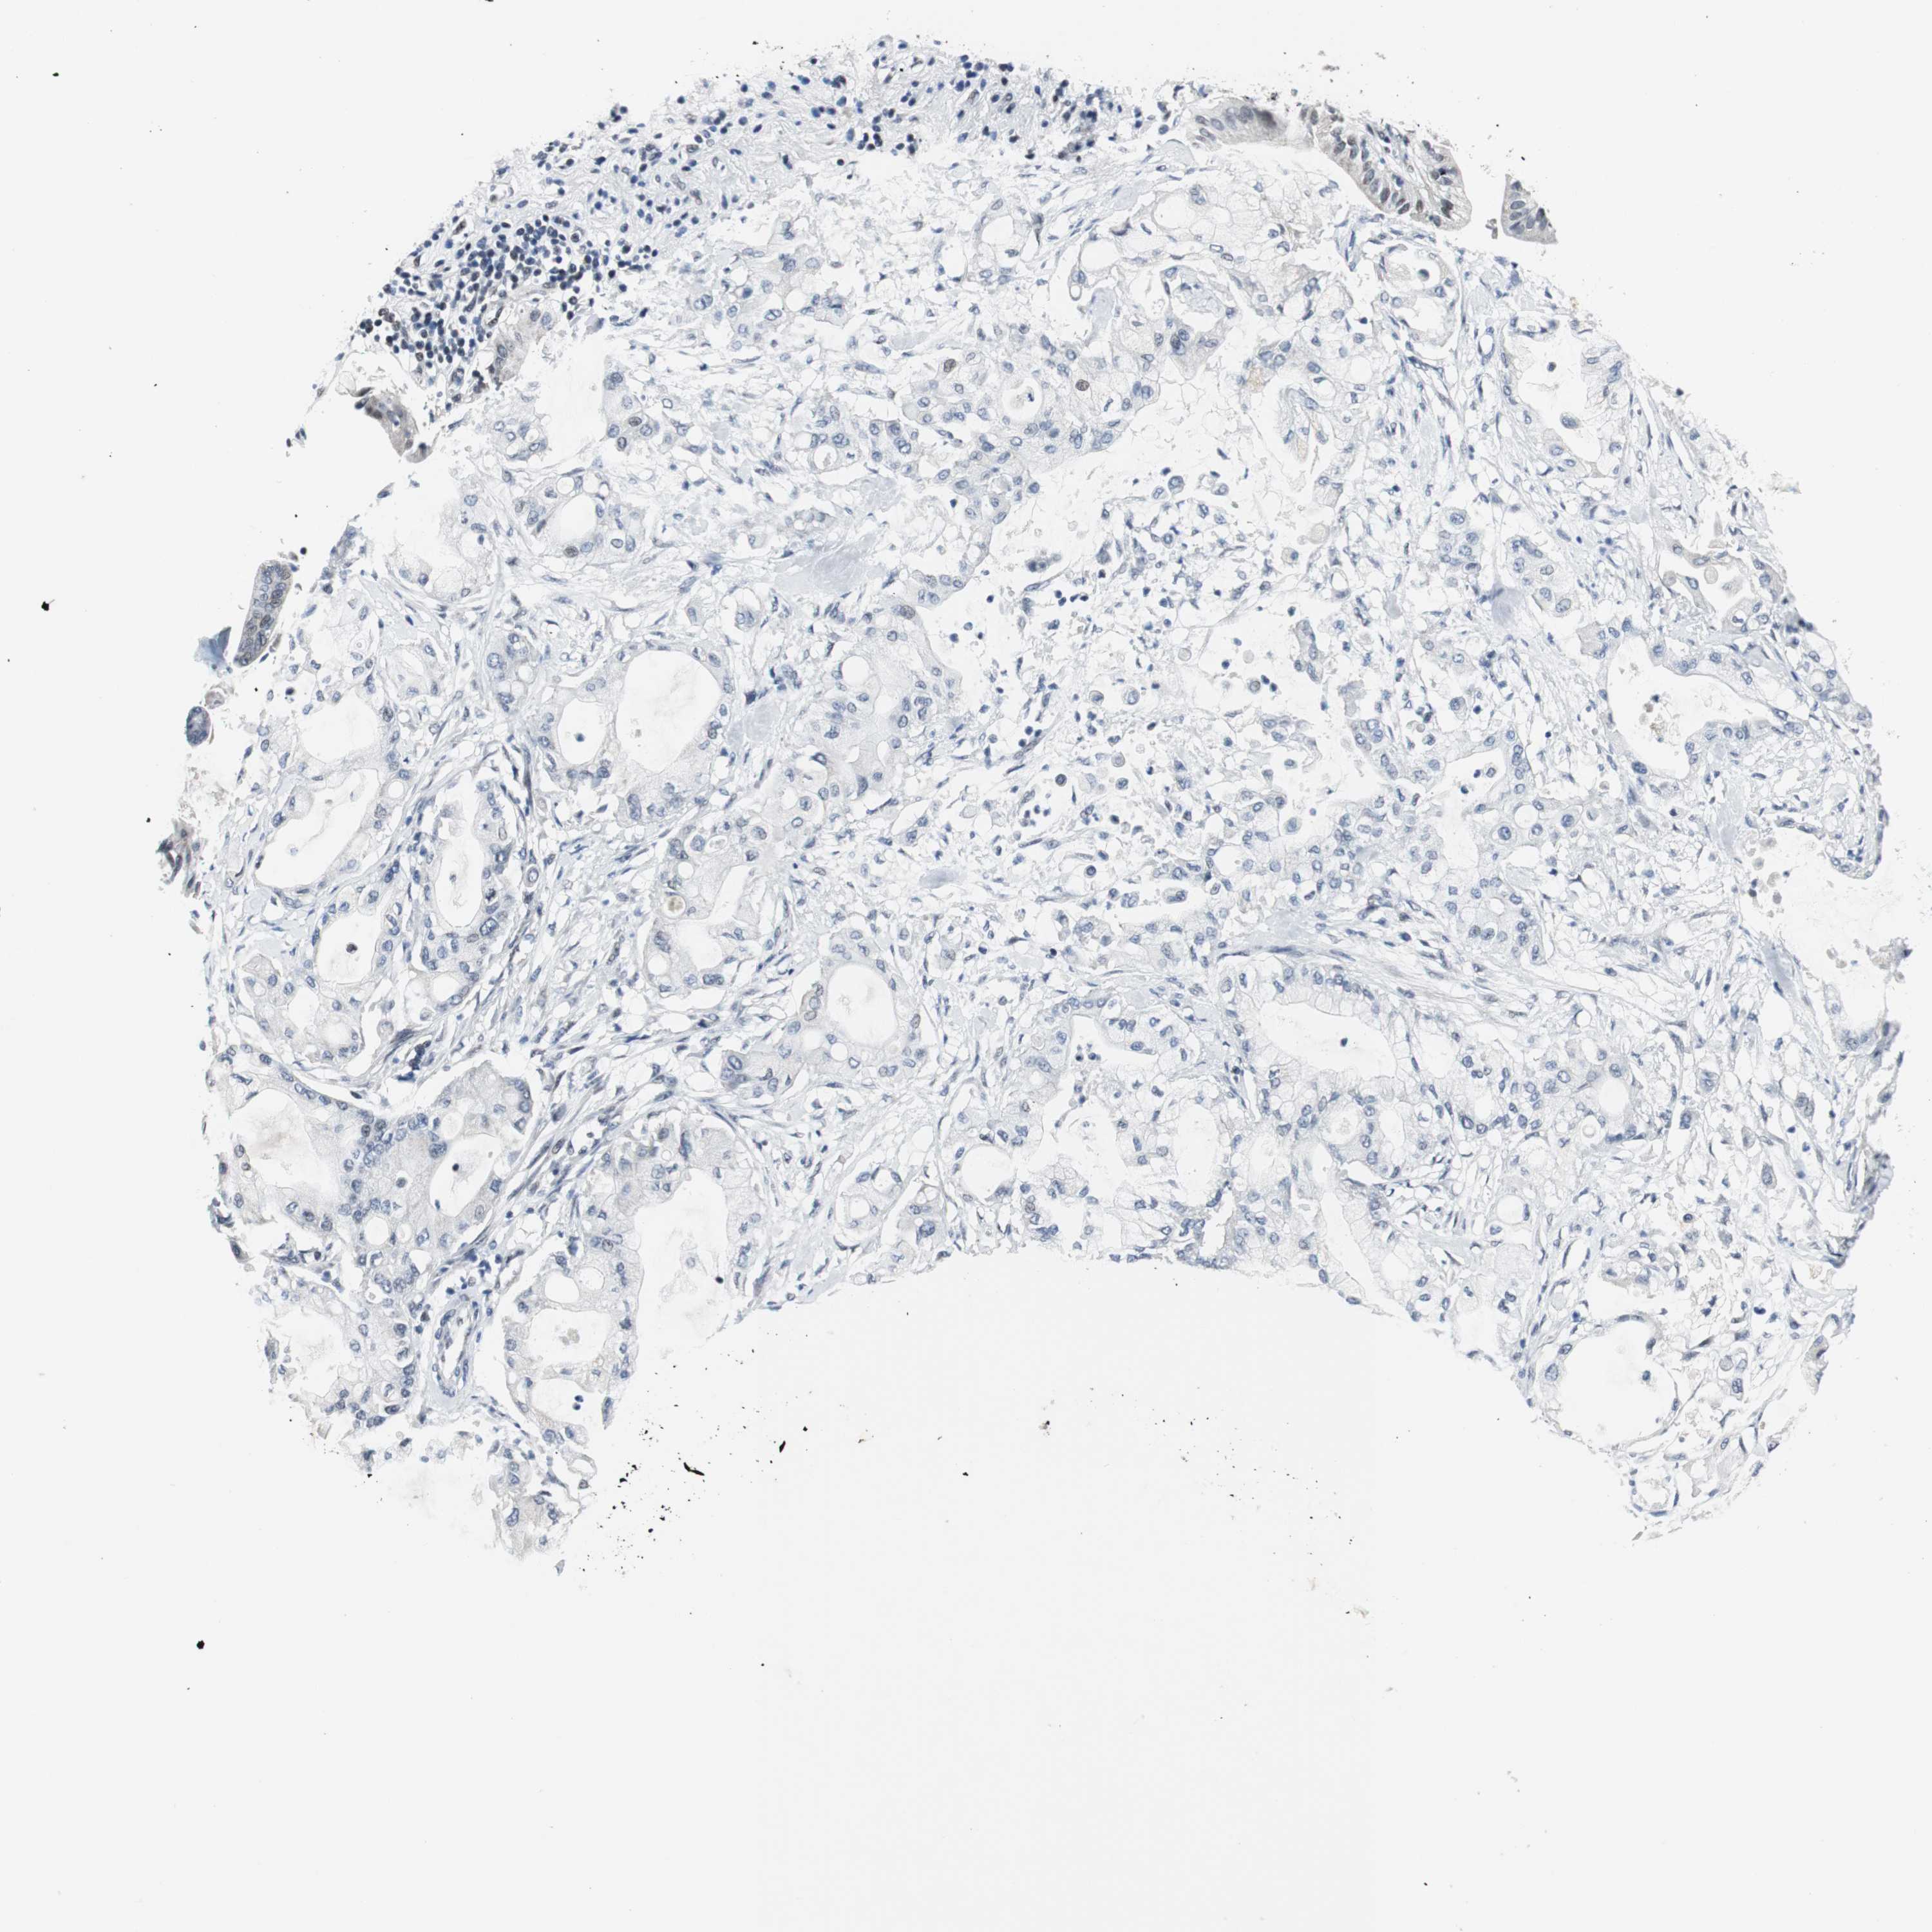

PANCREATIC CANCER - Protein expressioni

A mouse-over function shows sample information and annotation data. Click on an image to view it in a full screen mode. Samples can be filtered based on level of antibody staining by selecting one or several of the following categories: high, medium, low and not detected. The assay and annotation is described here.

Note that samples used for immunohistochemistry by the Human Protein Atlas do not correspond to samples in the TCGA dataset.

Antibody stainingi

Antibody staining in the annotated cell types in the current human tissue is reported as not detected, low, medium, or high, based on conventional immunohistochemistry profiling in selected tissues. This score is based on the combination of the staining intensity and fraction of stained cells.

Each image is clickable and will lead to virtual microscopy that enables deeper exploration of all samples and also displays staining intensity scores, fraction scores and subcellular localization as well as patient and tissue information for each sample.

Antibody HPA005544

Antibody CAB004508

Staining

High

Medium

Low

Not detected

Intensity

Strong

Moderate

Weak

Negative

Quantity

>75%

75%-25%

<25%

None

Location

Nuclear

Cytoplasmic/membranous

Cytoplasmic/membranous,nuclear

Adenocarcinoma, NOS

Adenocarcinoma, metastatic, NOS